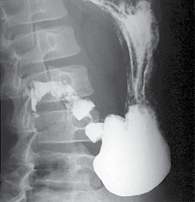

Рис. 4. Птоз желудка у больной с синдромом Эллерса – Данло: рентгенологическое исследование желудка и 12-перстной кишки с бариевым препаратом (желудок увеличен в объеме, натощак содержит большое количество слизи, нижний полюс желудка в малом тазу)

Особое значение приобретает состояние соединительной ткани. Так, диффузная дисплазия соединительной ткани (синдром Эллерса – Данло) не только является предпосылкой к развитию нарушений миофасциальных взаимоотношений, но и может провоцировать тяжелую патологию (рис. 4).